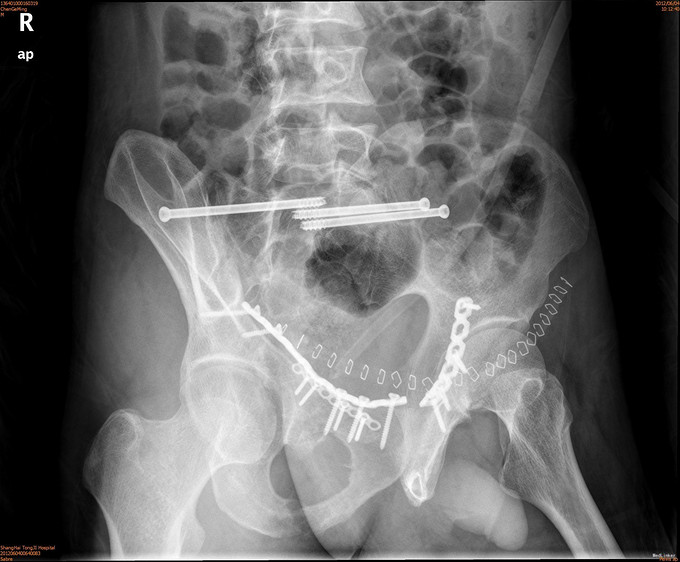

患者男,41岁,因车祸致双侧髂腰部、中下腹部及会阴部疼痛,伴尿道出血1小时。患者于1小时前不慎被汽车撞伤,当即感到双侧髂腰部、中下腹部及会阴部剧痛,尿道口有鲜血渗出,有昏迷,后自行苏醒,120送入我院急诊,CT示两侧骶髂关节前缘骨折,双侧耻骨上下支骨折,周围血肿形成。急诊导尿失败,遂入院治疗。

诊断为耻骨上下支骨折,兄弟科室会诊治疗结束后,患者病情稳定,行切开复位内固定术。